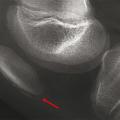

Ostéochondrose apophysaire de la rotule

FRACTURES OSSEUSES

ENFANT

EXERCICE PHYSIQUE

Image